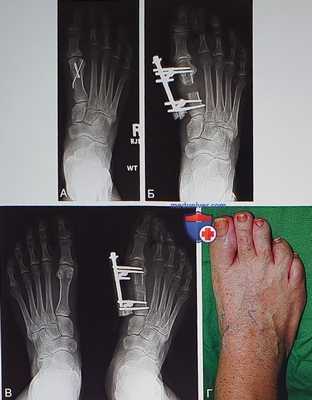

• На рис. 17 показан наружный фиксатор, используемый для удлинения четвертой плюсневой кости, через четыре недели после операции

• На рис. 18 представлены несколько рентгенограмм в процессе удлинения четвертой плюсневой кости:

Рентгенография назначается через 10 дней после операции и через семь дней после начала дистракции (рис. 18, А)

Рентгенография назначается через три недели после начала дистракции (рис. 18, Б)

Рентгенография назначается через семь недель после начала дистракции (рис. 18, В)

Рентгенография назначается после снятия фиксатора, что обычно делают через 10 недель (рис. 18, Г)

На рис. 18, Д представлена рентгенограмма через два года после операции. Обратите внимание на некорригированную деформацию четвертого пальца

Клинически определяется легкая латеральная девиация четвертого пальца (рис. 18, Е)

• Внешний вид стопы с наложенным фиксатором (рис. 20, А)

• Рентгенограмма после 10 дней компрессии и через три недели после дистракции (рис. 20, Б)

• Рентгенограмма через шесть недель после дистракции (рис. 20, В)

• Рентгенограмме через 11 недель после дистракции (рис. 20, Г)